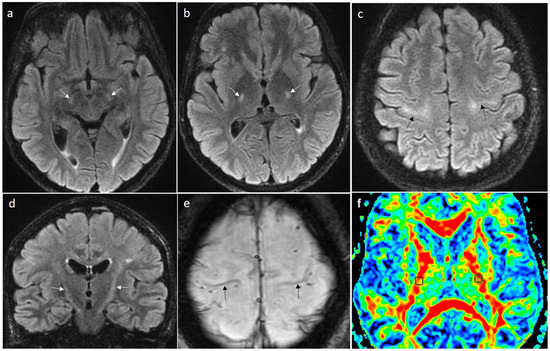

Establishing Diagnostic and Differential Diagnostic Criteria for Amyotrophic Lateral Sclerosis

by Edyta Dziadkowiak, Karol Marschollek, Anna Kwaśniak-Nowakowska, Anna Zimny, Wiktoria Rałowska-Gmoch, Małgorzata Boroń and Magdalena Koszewicz

J. Clin. Med. 2026, 15(1), 287; https://doi.org/10.3390/jcm15010287 - 30 Dec 2025

Motor neuron disease (MND) represents a broad and heterogeneous group of disorders involving the upper or lower motor neurons, represented mainly by amyotrophic lateral sclerosis (ALS), primary lateral sclerosis (PLS), progressive muscular atrophy (PMA) and progressive bulbar palsy (PBP). Primary motor neuronopathies are [...] Read more.

Motor neuron disease (MND) represents a broad and heterogeneous group of disorders involving the upper or lower motor neurons, represented mainly by amyotrophic lateral sclerosis (ALS), primary lateral sclerosis (PLS), progressive muscular atrophy (PMA) and progressive bulbar palsy (PBP). Primary motor neuronopathies are characterized by progressive degenerative loss of anterior horn cell motoneurons (lower motor neurons) or loss of giant pyramidal Betz cells (upper motor neurons). Rare atypical variants of MND-ALS include flail arm syndrome (FA), flail leg syndrome (FL), facial-onset sensory and motor neuronopathy (FOSMN), finger extension weakness and downbeat nystagmus motor neuron disease (FEWDON-MND) and long-standing and juvenile MND-ALS. In this article, we present a review of diagnostic criteria and the differential diagnosis for MND, focusing on ALS. Full article